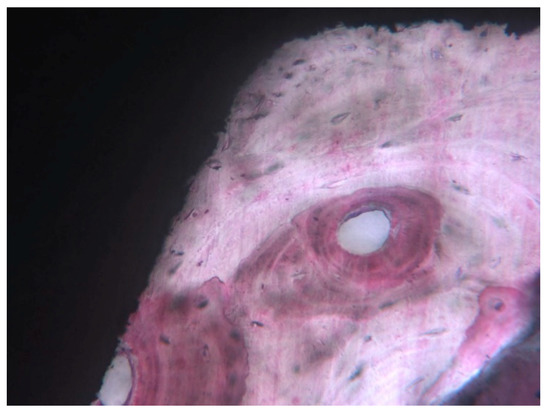

3. Results